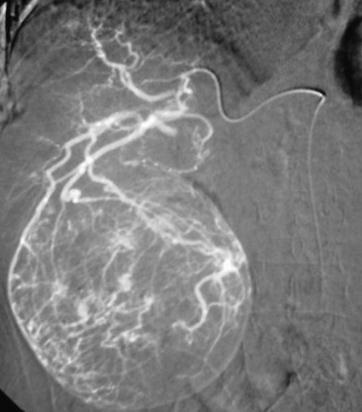

当肿瘤比较局限,导管可以前进至段或者亚段动脉,从而只对存在肿瘤区域进行化学栓塞。使用这项技术时推荐使用共轴的微导管。整体肿瘤区域是否完全被导管栓塞可以从动脉造影中估计,但是,从导管内注入造影剂时进行动脉造影CT可以得到更准确的评价。

碘化油的量取决于肿瘤的大小和血管分布,导管置入部位,和肝功能受损情况。一般剂量为3至10毫升。在靶动脉内放置的导管内注射2%的利多卡因5ml后再进行化学栓塞注射。这样可以避免在操作过程中或操作刚结束时肝脏内产生的剧烈疼痛。然后,抗肿瘤药物与碘化油的混合物被缓慢注入。最后,被剪成小块状的明胶海绵或海绵颗粒或PVA与造影剂和少量的抗肿瘤药物的混合物注入肝动脉。如果存在肝外侧支动脉,则在此动脉中也应放置导管,进行化学栓塞。如果存在显著的动-门脉短路,则在注入碘化油乳剂前,应首先注入少量明胶海绵以阻断血流。动-肝静脉短路也应该被同样处理,但在注入碘化油之前寻找是否有到体循环的短路是最重要的,避免肝动脉栓塞后的肺栓塞。 注入碘化油乳剂之后,应进行数字减影血管造影(DSA),从而确定肿瘤染色是否已经消失。术后定期应拍摄腹部X线片,以确定碘化油是否持续沉积。

碘油乳剂的栓塞终点:新生血管的阻塞,意味着应避免肿瘤滋养动脉出现血流停滞。对于常规TACE来说栓塞时知道门静脉分支可见时是最理想的。而对于DEB-TACE,我们需要血流载运微球,所以心脏两、三跳之后造影剂消失。

最理想的是栓塞时门静脉分支可以看见